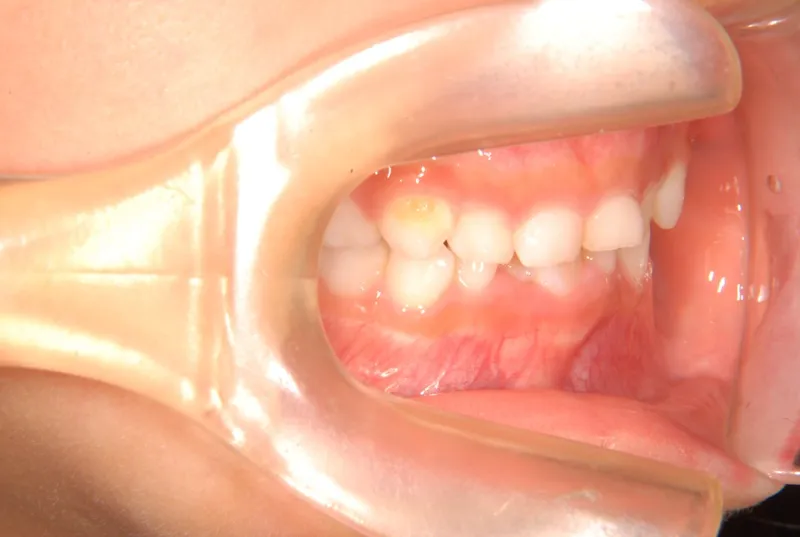

【子供の矯正(一期)】叢生・早期治療・6歳女児【S.T様】

初診時年齢 6歳まで (女性) 主訴 ガタガタ

診断名 叢生 装置名

拡大床

下の歯がずれて生えています。

こどもの歯は下の2本しか抜けていませんが、放っておくとガタガタがきつくなるので、早い段階からの治療としました。

初診